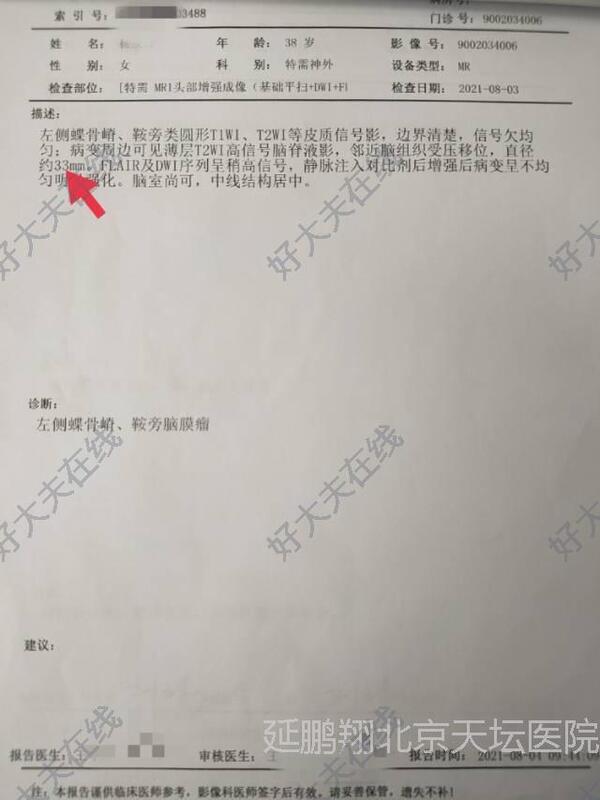

患者女性,38岁。间断性头痛3年左眼视力模糊1年。核磁显示左侧前床突脑膜瘤。

患者恢复顺利。复查核磁肿瘤消失。